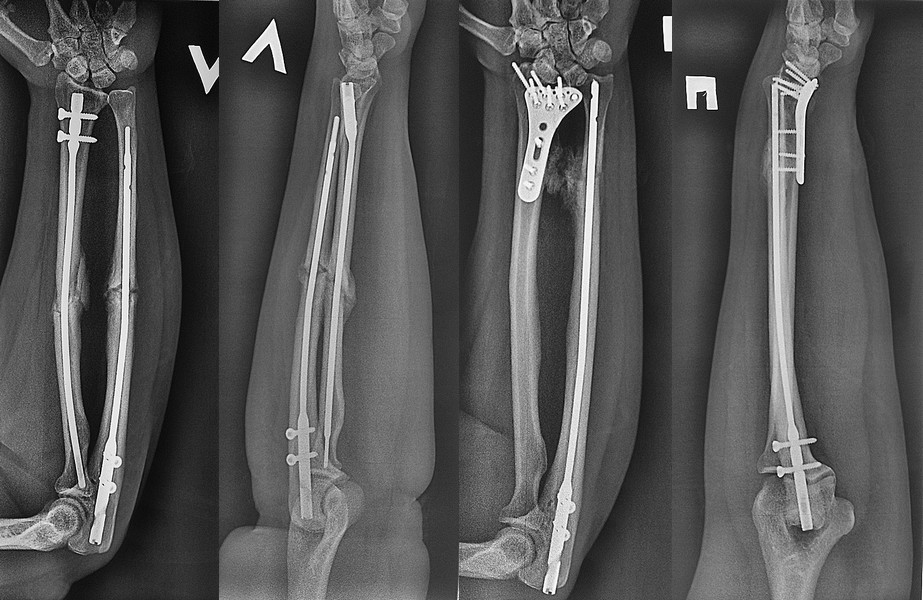

Пациентка, 40 лет, в составе политравмы получила закрытые переломы обоих предплечий. Два месяца назад выполнили CRIF правого предплечья штифтами. Левую локтевую кость CRIF штифтом и дистальный метаэпифиз лучевой кости ORIF волярной пластинкой. Индометацин не получала.

Движения в правом предплечье в полном объеме. В левом ограничение ротации (супинации) наполовину от положенного. Связываю это с образованием межкостной оссификации (синостозированием). Кто как это лечит? Прошу помощи в разработке реабилитации.